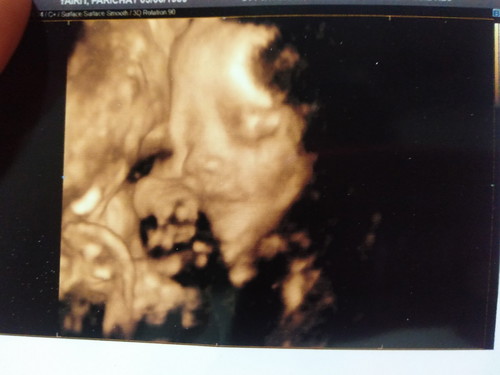

ผ่าคลอด+ทำหมัน

พรุ่งนี้หมอนัดผ่าคลอด+ทำหมัน.ทั้งตื่นเต้น.ทั้งกลัว.ทั้งกังวล จะได้เจอหน้ากันแล้วคนแปลกหน้าที่อยากเจอที่สุด

น้องก็รอเจอคุณแม่แล้ว